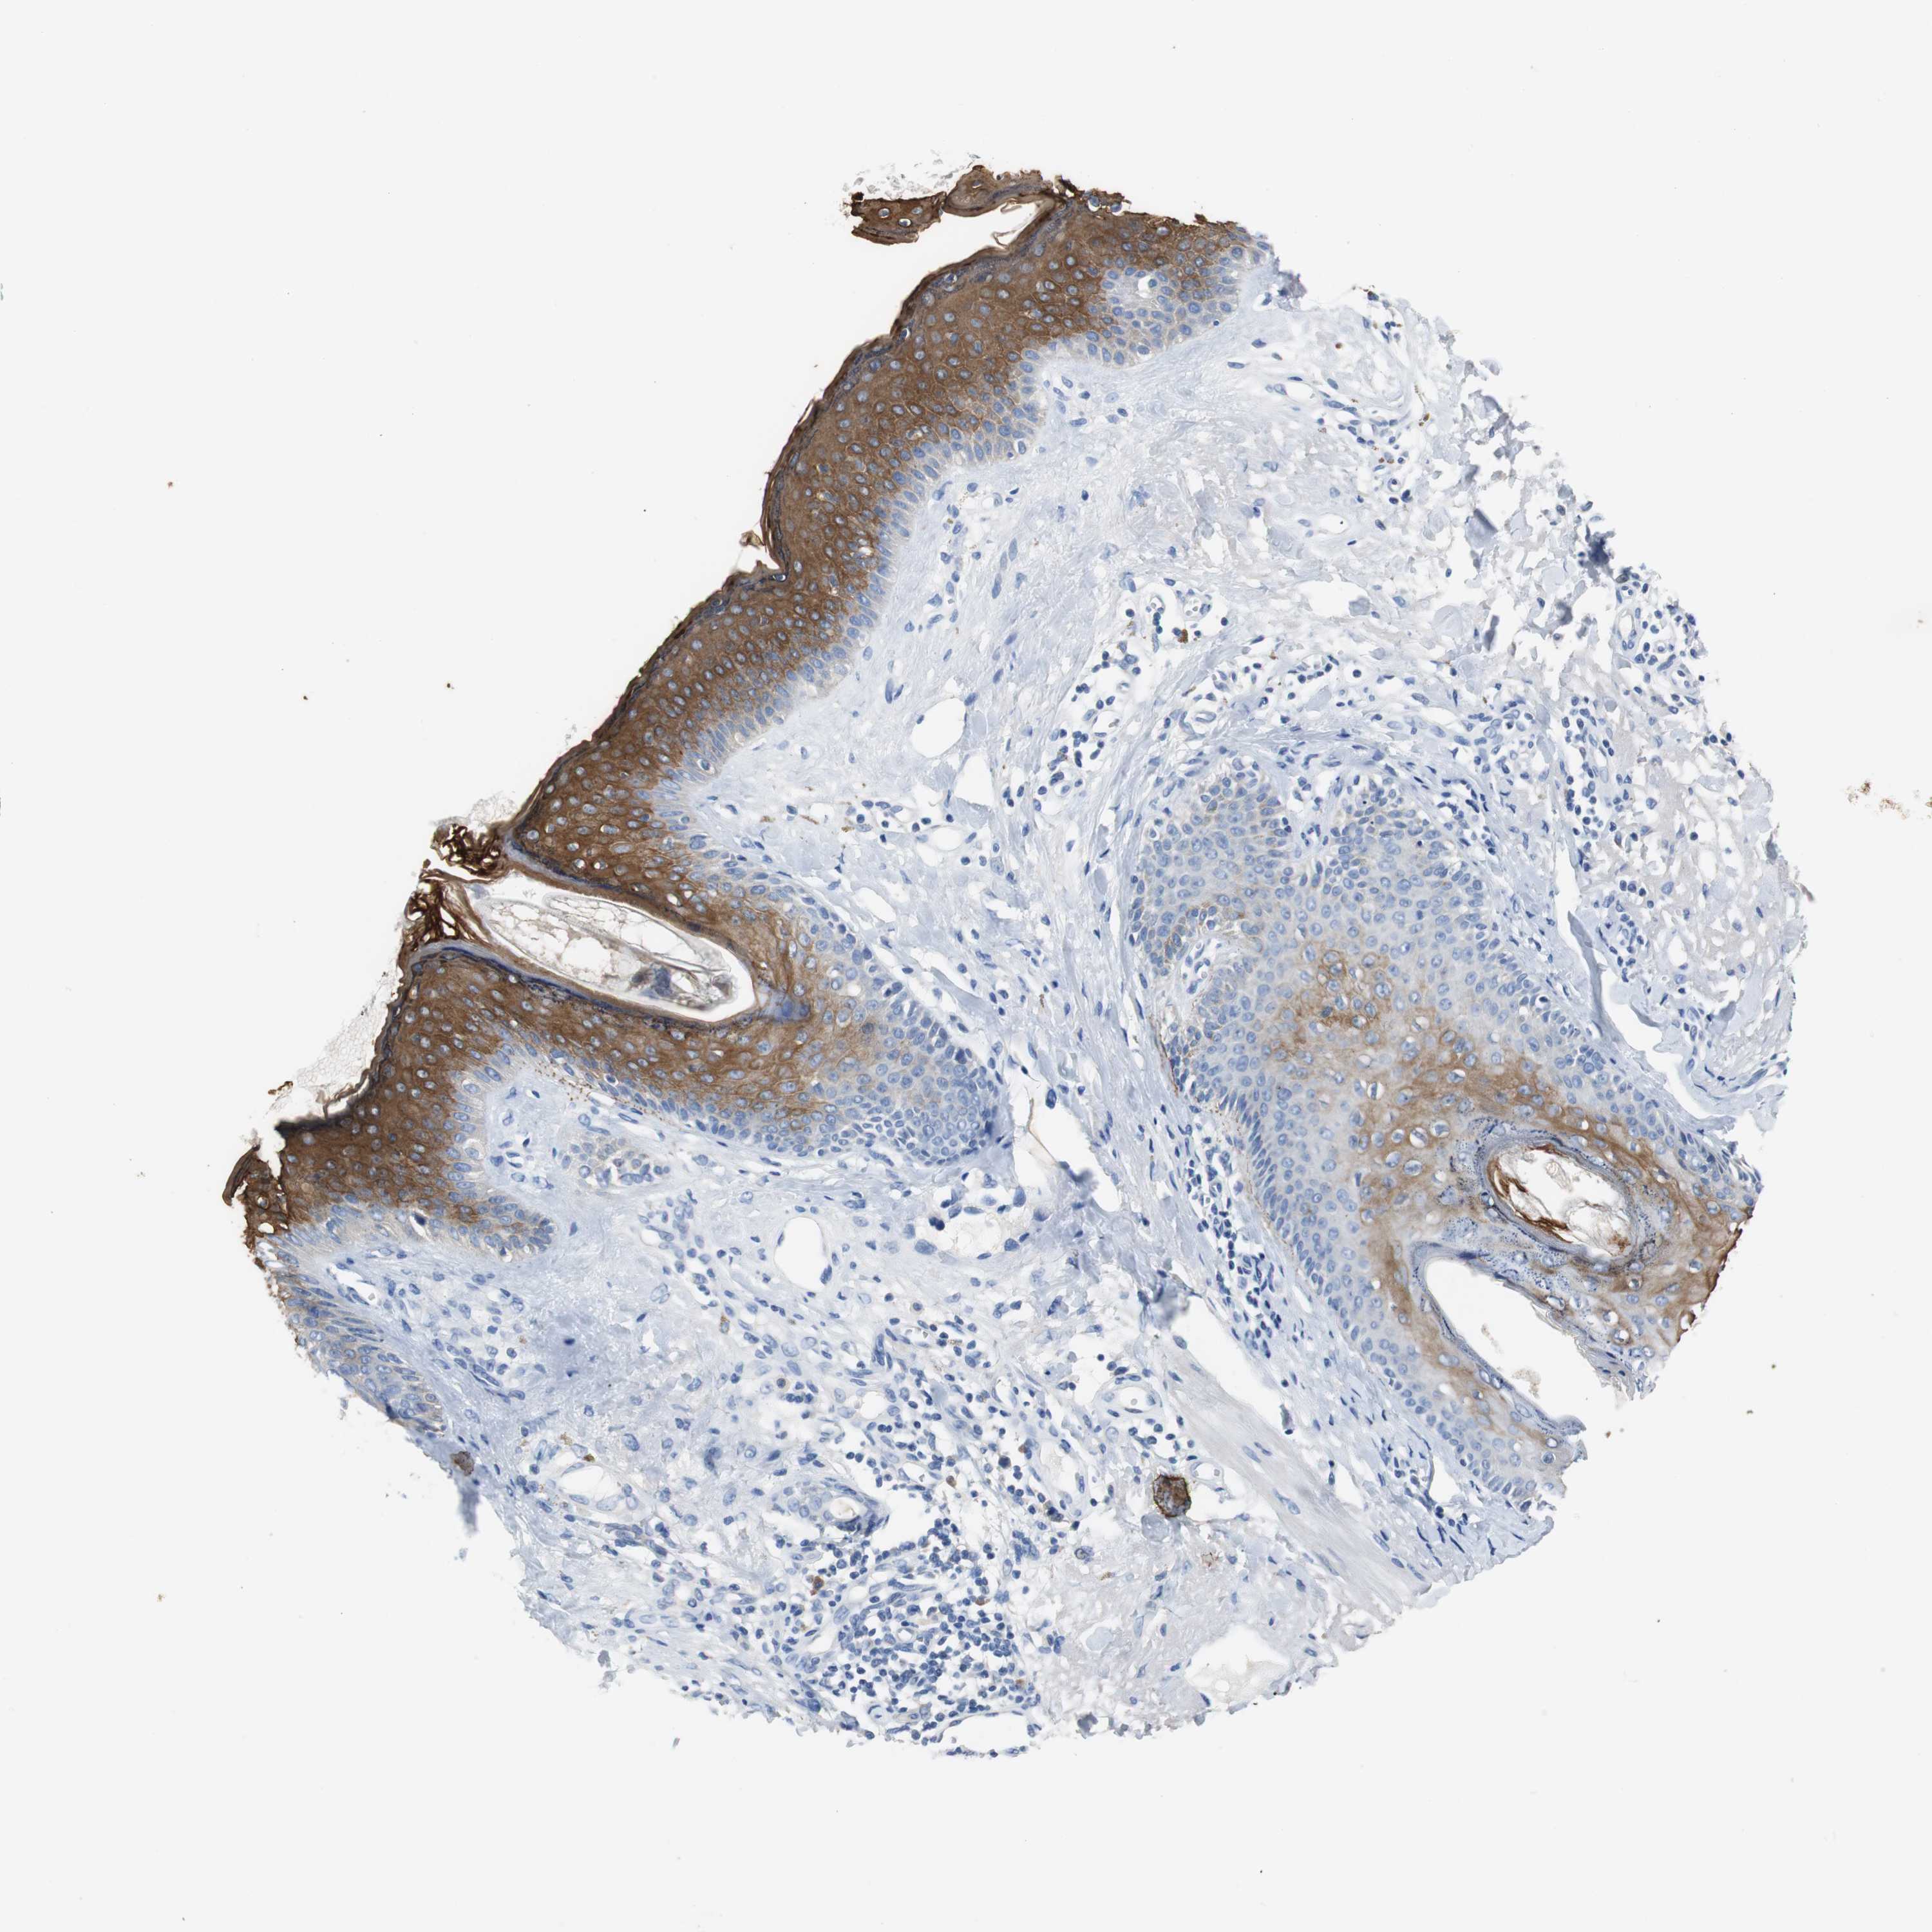

SKIN CANCER - Protein expressioni

A mouse-over function shows sample information and annotation data. Click on an image to view it in a full screen mode. Samples can be filtered based on level of antibody staining by selecting one or several of the following categories: high, medium, low and not detected. The assay and annotation is described here.

Antibody stainingi

Antibody staining in the annotated cell types in the current human tissue is reported as not detected, low, medium, or high, based on conventional immunohistochemistry profiling in selected tissues. This score is based on the combination of the staining intensity and fraction of stained cells.

Each image is clickable and will lead to virtual microscopy that enables deeper exploration of all samples and also displays staining intensity scores, fraction scores and subcellular localization as well as patient and tissue information for each sample.

Antibody HPA006507

Basal cell carcinoma